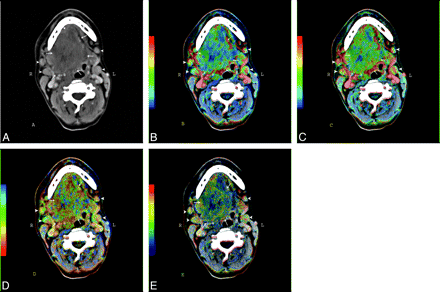

Nineteen patients (17 men, 2 women) with oropharynx SCCA were included in our study. The mean patient age was 55.6 ± 9.2 years. The tumors were staged according to the TNM staging system (Table 1). All patients were examined before chemotherapy and during follow-up with routine contrast-enhanced CT (CECT) scans of the neck. The PCT studies of the neck were performed at the time of the baseline CECT examination. Figure 1 shows an illustrative example of the perfusion parametric maps in a patient with advanced SCCA in oropharynx and oral cavity. The patients underwent endoscopy (if needed, with biopsy) after the baseline CT examination (before induction chemotherapy); at the time of the second examination (after the induction chemotherapy); and during the routine follow-up control, which (according to our protocol) was performed every 3 months for the first year, followed by every 4 months in the second year or on symptom deterioration. Baseline CECT and PCT studies were performed 1.4 ± 0.5 days (95% confidence interval [CI], 1.1–1.6 days) before baseline endoscopy. The mean time between the baseline radiologic examination and the first CECT scan after the completion of the induction chemotherapy was 76.0 ± 4.6 days (95% CI, 68.9–83.1 days).

CECT (A) and PCT parametric maps (B-E) of a male patient with SCCA carcinoma in the oropharynx and oral cavity (arrows) as well as enlarged lymph nodes (arrowheads) in Levels I and II on both sides. B, BF map. C, BV map. D, MTT. E, PS map.